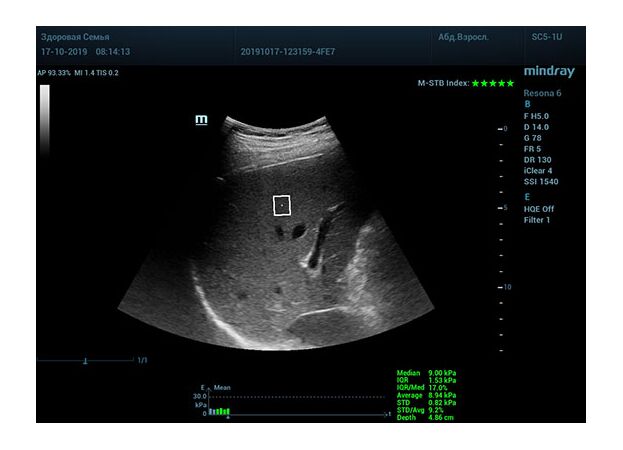

Определение плотности печени. Не ошибся ли оператор при измерении эластических свойств печени? Для оценки критериев качества предусмотрен индекс MBT, который покажет насколько «твердой» была рука оператора и двигалась ли печень. При MBT 5* рука тверда и показатели достоверны. Для оценки качества результатов используется IQR индекс, отображающий колебания показателей в точке измерения при расчете медианы. Показатели при IQR <30% считаются приемлемыми. Техника сканирования через межреберные промежутки требует размещение окна интереса на несколько сантиметром ниже капсулы, для исключения эффекта реверберации. Установка ROI на паренхиму без захвата сосудов, для исключения погрешностей измерения.

Стадия фиброза определяется по системе METAVIR Staging, построенной на данных биопсии и сопоставлении с данными эластографии. Своевременная диагностика фиброза, и начало его лечения, залог благоприятного исхода заболевания.